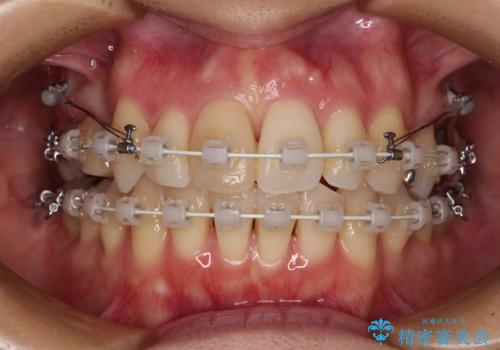

上顎前歯の歯軸が顕著に改善され、非常に口の閉じやすい歯列に仕上げることができました。